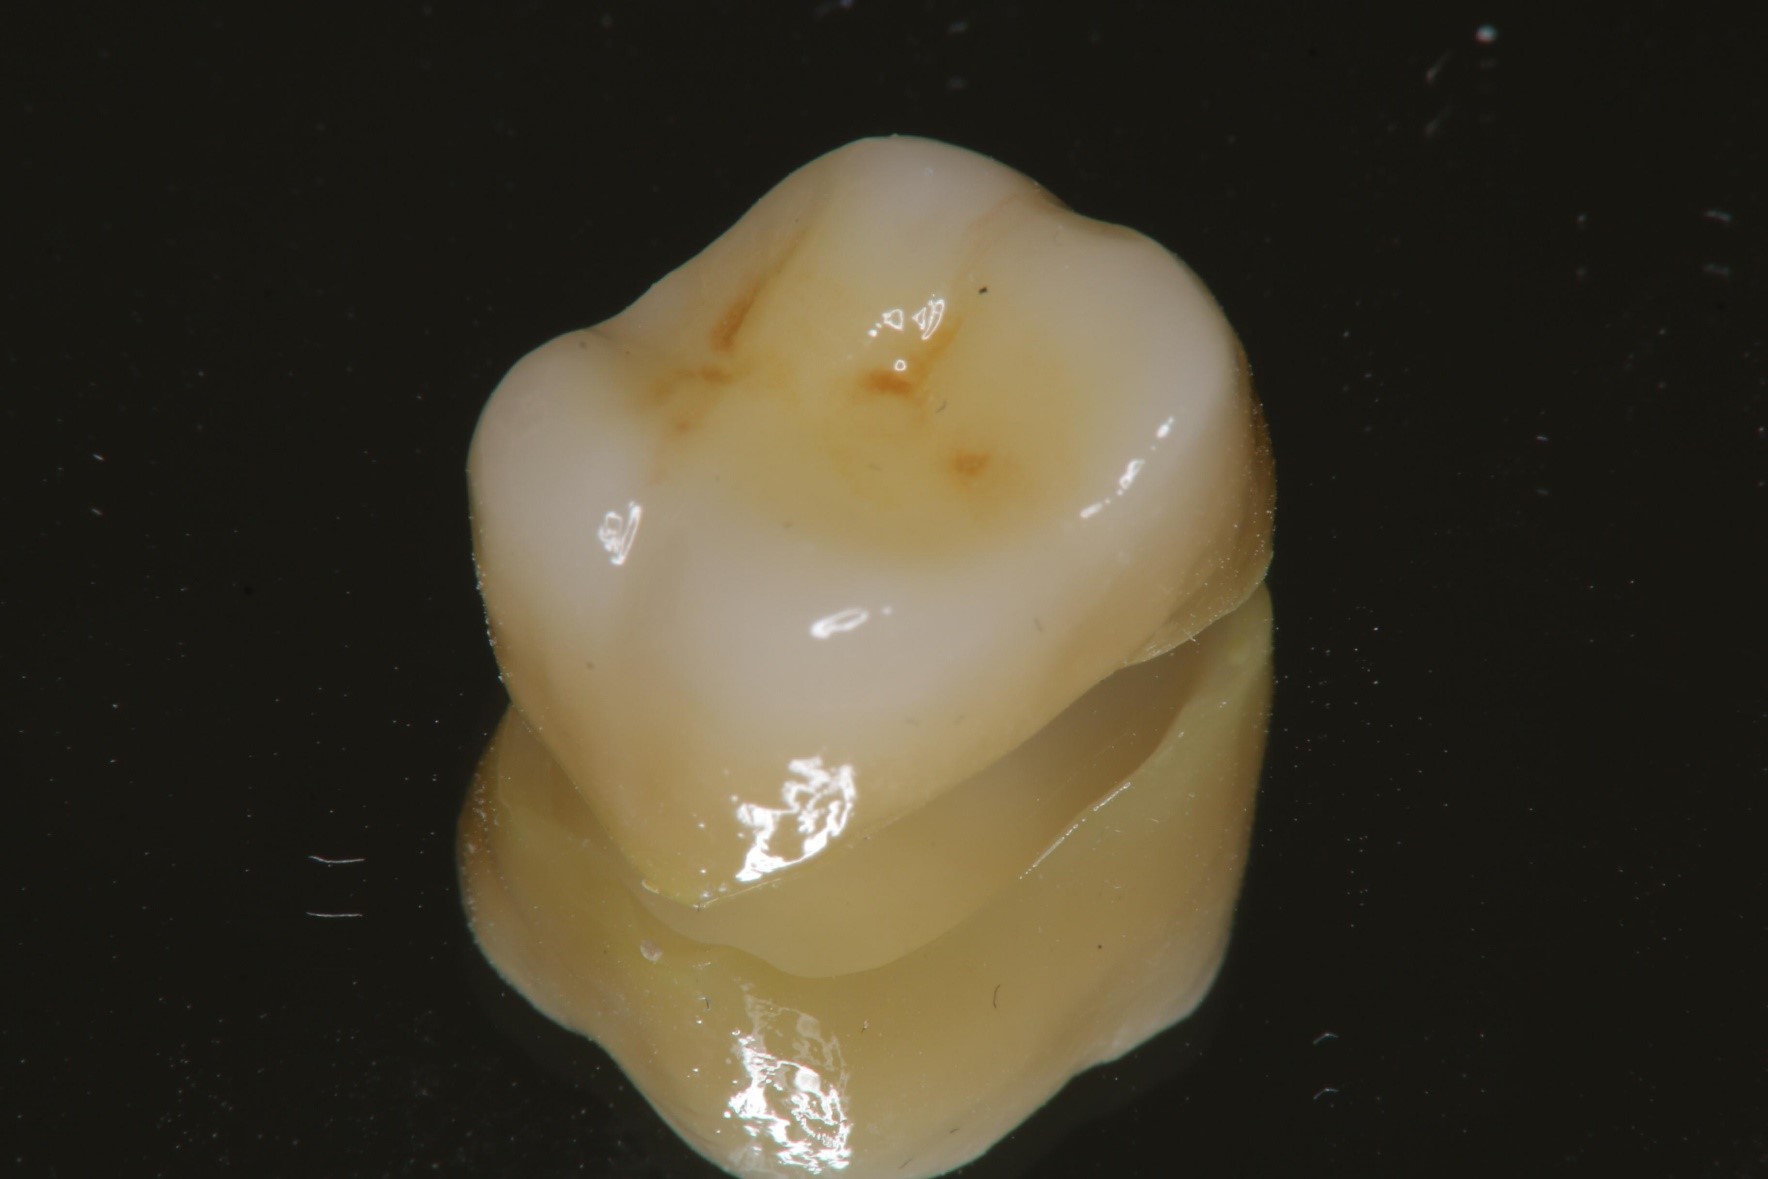

全鋯冠